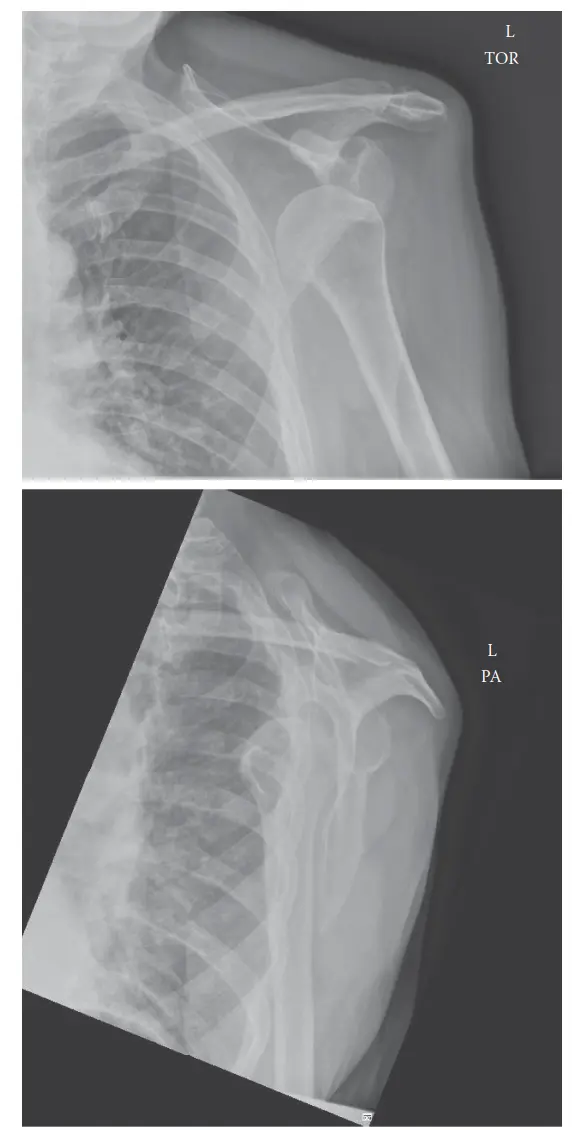

الأشعة السينية (Plain Radiographs):

- تُعد الأشعة السينية القياسية (الجانبية، المحورية، Y-scapular) ضرورية لتأكيد حدوث الخلع، وتحديد ما إذا كان هناك أي كسور مصاحبة في التجويف الحُقّي (آفة بانكارت العظمية) أو في رأس عظم العضد (آفة هيل-ساكس).

- قد تُستخدم لقطات خاصة مثل "Stryker notch view" لتحسين رؤية آفة هيل-ساكس، و"West Point axillary view" لرؤية أفضل لآفة بانكارت العظمية.